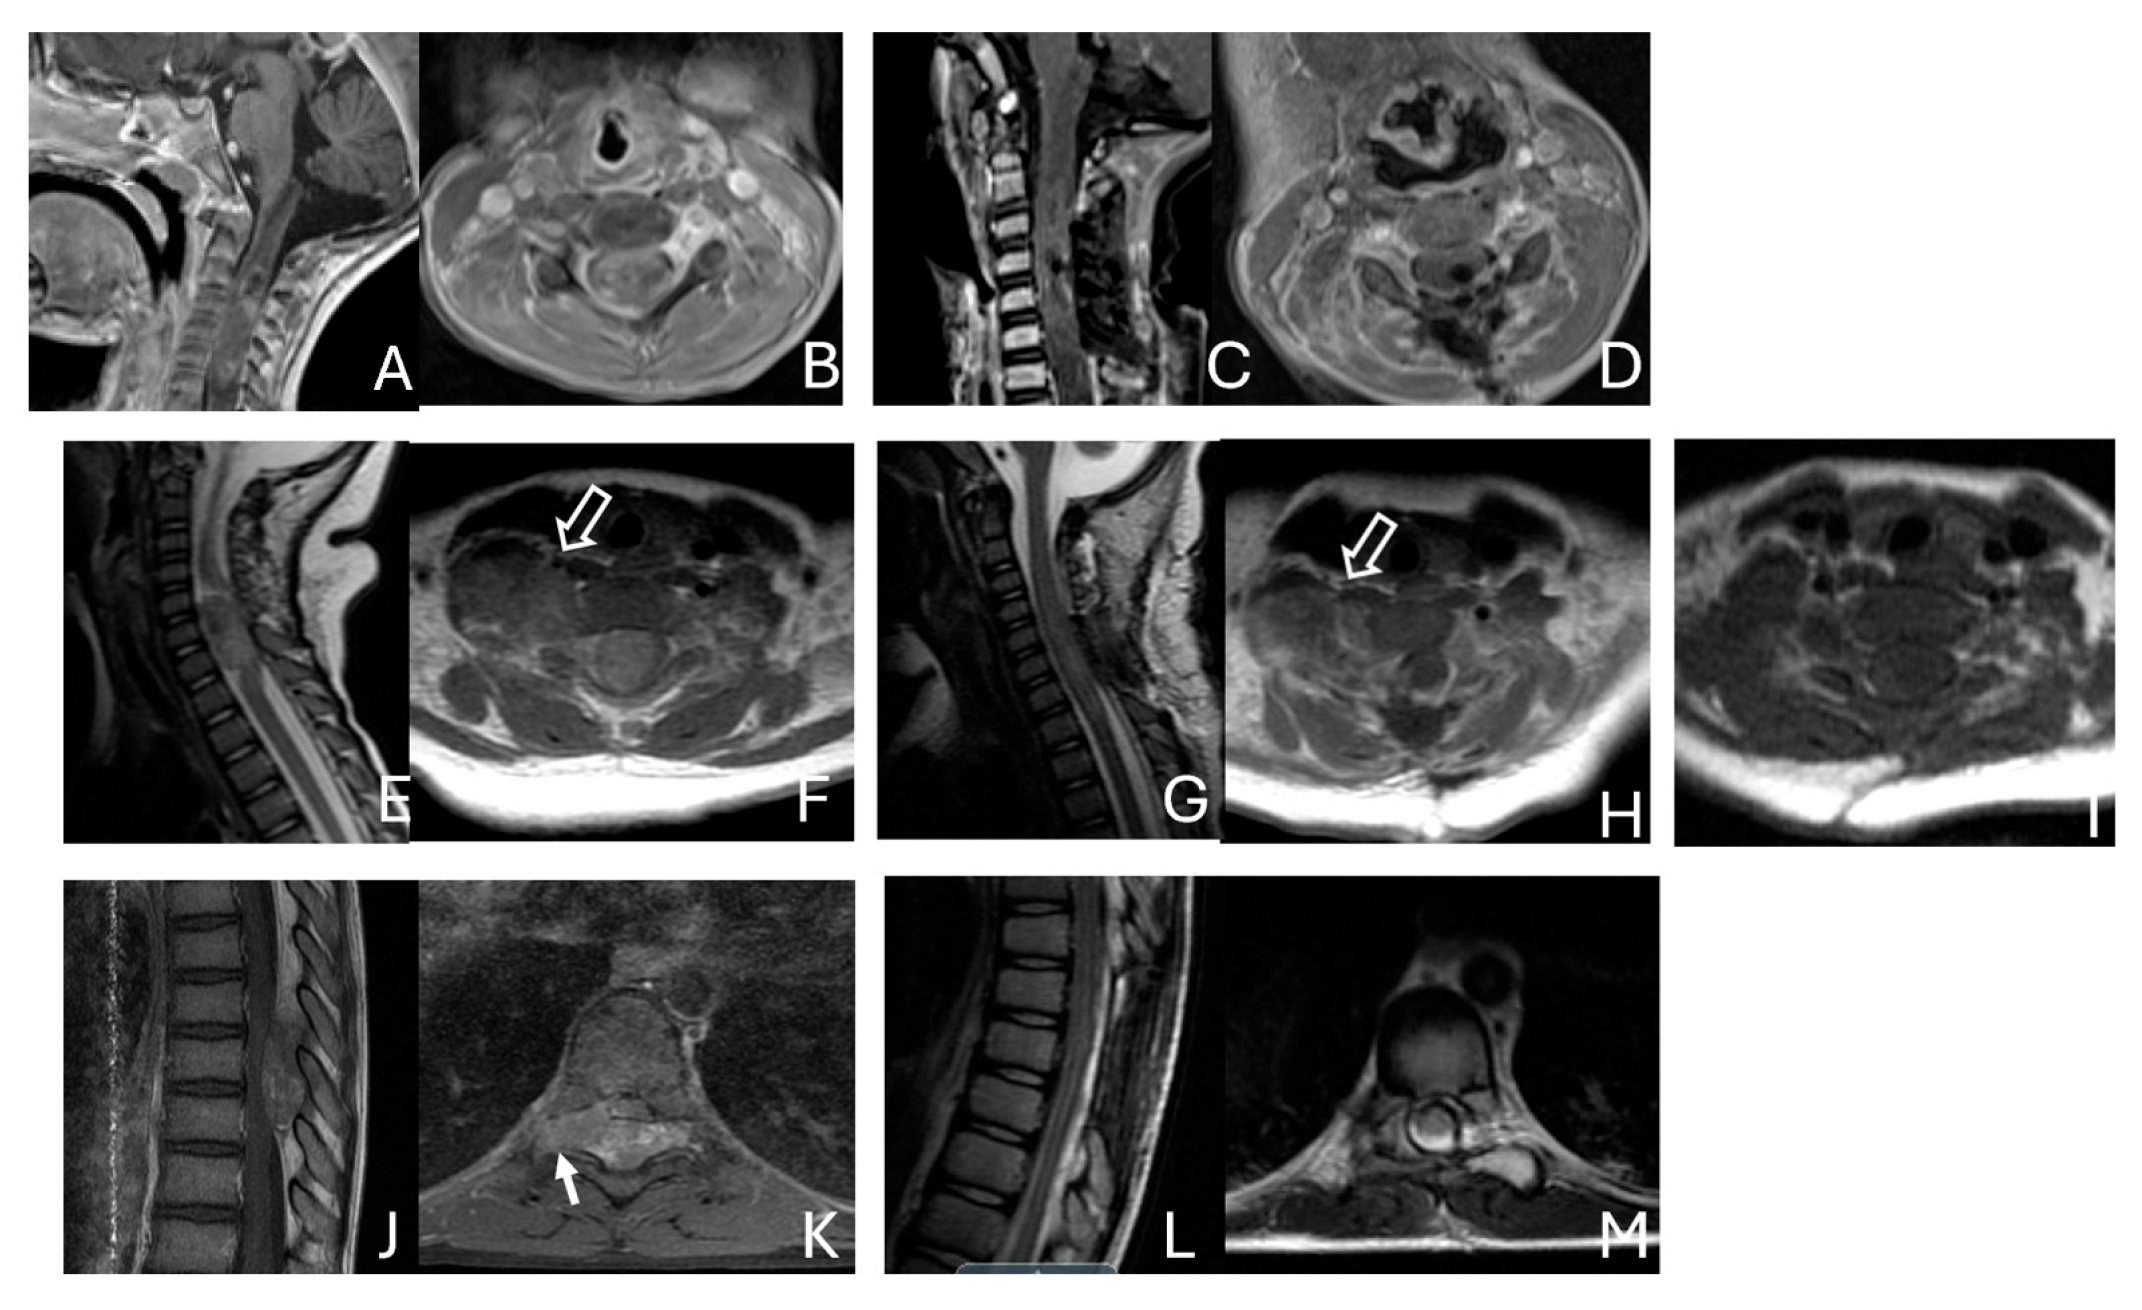

Figure 3.

Basal ganglia ATRT. (A–D): Post contrast MR images ((A)-axial, (B)-coronal) of 13-month-old boy with deep seated ATRT. Note the solid tumor with peritumoral cysts at the basal ganglia with one cyst extending to the thalamus. Post-resection MR images ((C)-axial, ((D)-coronal) show the tumor resected cavity in the basal ganglia with the thalamus clear of tumor involvement. (E–H): Post contrast MR images ((E)-axial, (F)-coronal) of a 23-month-old boy with a large ATRT of deep temporal lobe and the insula extending to the basal ganglia. The tumor was predominantly in the basal ganglia as shown postoperative MR ((G)-axial, (H)-coronal).